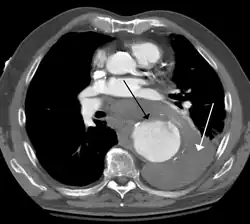

Contrast enhanced CT of a ruptured large (7 cm) thoracic aneurysm, with black arrow indicating the aorta, and white arrow blood in the thorax